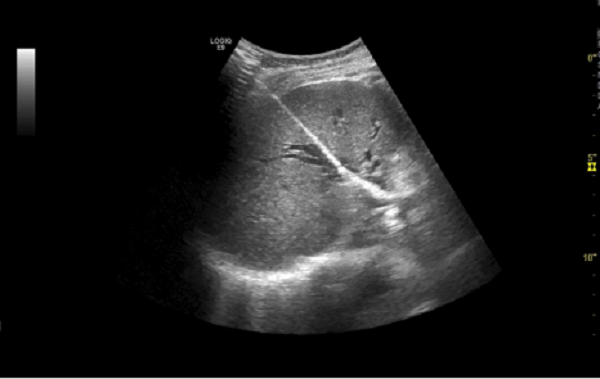

为了解决这个难题,我院普外科主任钟世洪团队和超声诊断科主任丁发辉团队经过严密讨论,拟定患者在全麻状态下行PTCD术,经彩超引导,置入右肝管,穿刺成功后右肝管引流出约120ml白胆汁。